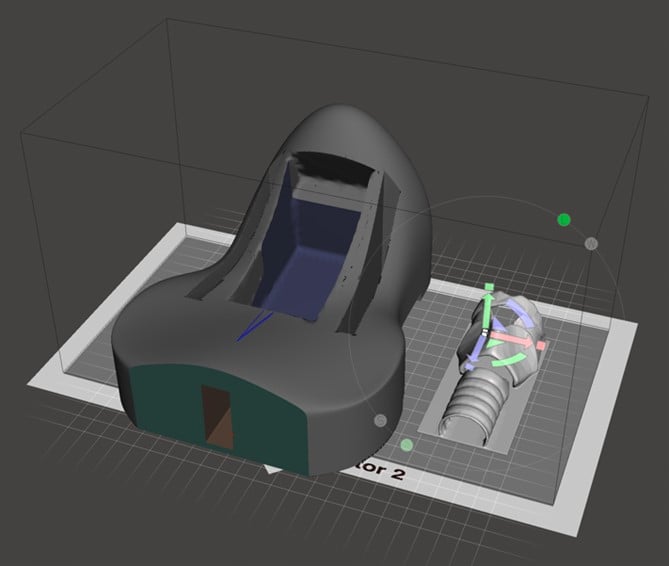

3-D printable designs for cricothyrotomy using the palpation method have been available for free for educational purposes online. Using a free download computer design program, a 3-D model of the neck was redesigned to allow for greater pre-tracheal soft tissue, to create a model where palpation of the landmarks for performing cric is difficult or impossible. This model was converted into a format to be printed on a 3-D printer. The 3-D printable components of this model can be found for free download for educational use on Thingiverse.com by searching for ultrasound guided cric trainer.

Figure 5. Computer model of neck and larynx as components of a task trainer for ultrasound-guided cricothyrotomy